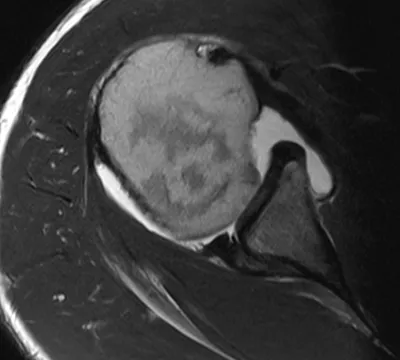

SLAP tear

Arthrogram

4/11/2026